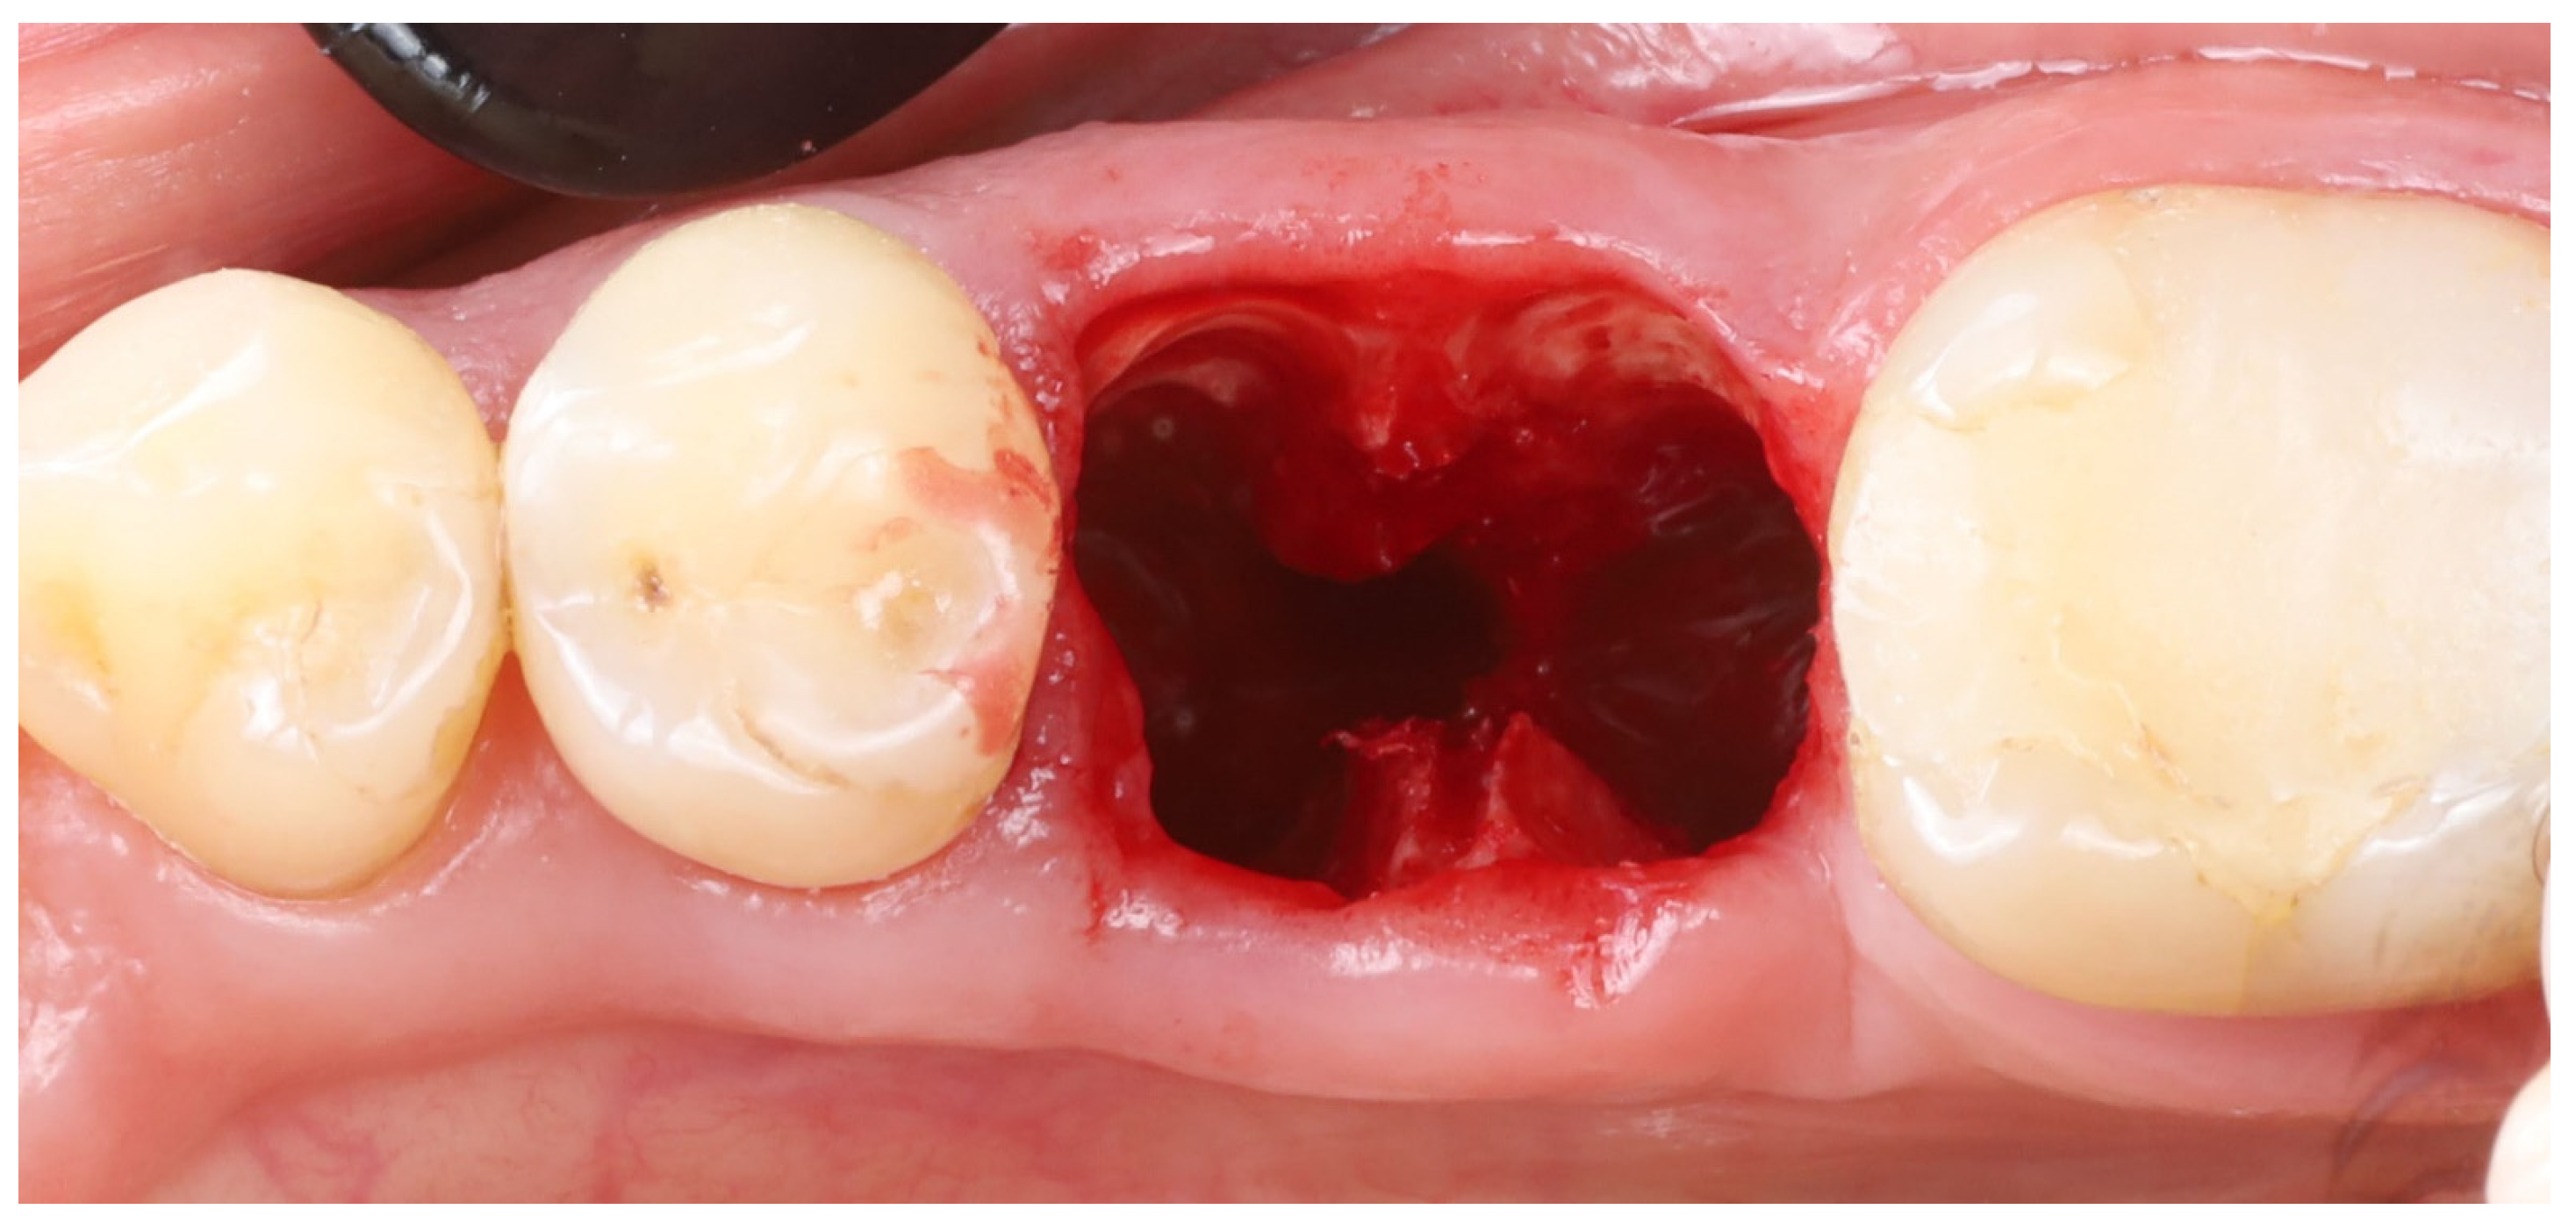

- 10.

- Implant osteotomy preparation: An implant osteotomy was created in the inter-radicular septum (furcation bone) of the extraction site [16]. Sequential drilling (using the standard Blue Diamond implant drill kit to the 4.3 mm diameter, Megagen, South Korea) was performed. Care was taken to angle the drills to stay in the middle of the socket and avoid encroaching on the buccal or lingual plates. The osteotomy was prepared to a depth such that the future implant platform would be positioned about 5–6 mm apical to the original buccal gingival margin (as estimated from the CBCT and clinical measurements). This depth was planned to place the implant platform approximately 3–4 mm below the alveolar crest and ~6 mm below the gingival margin once the implant was in place (accounting for the soft tissue height).

- 11.

- Implant placement: A dental implant (Megagen Blue Diamond, 4.8 mm diameter × 10 mm length, conical “Deep thread” design) was inserted into the prepared osteotomy. The implant was centered within the socket, with its shoulder positioned roughly 5–6 mm below the level of the surrounding gingival margin (Figure 4). The implant fits snugly between the two buccal shields without exerting undue pressure on them. Primary stability was achieved; the implant had an insertion torque of about 35 N·cm, and verification with a resonance frequency analysis device showed an Implant Stability Quotient (ISQ) exceeding 70. (This high primary stability indicated that the implant was well stabilized in the septal bone despite the immediate placement.)